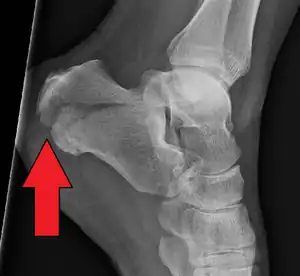

![]() | |

| X-ray of a fractured calcaneus | |